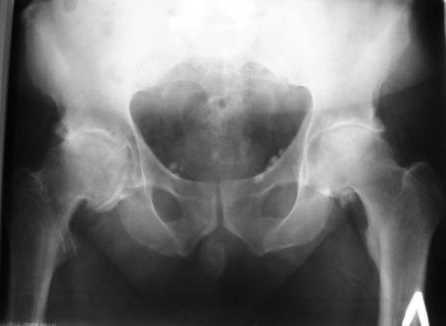

Больной Т. 56 лет, Диагноз: двухсторонний коксартроз 3-4 ст справа, 1-2 ст слева 2.10.08 выполнена операция тотальное бесцементное эндопротезирование. Использовался наружный доступ, положение на боку. Операция протекала без особенностей.

Выполнен послеоперационный ренгеноконтроль в прямой проекции. Рана зажила.

Уважаемый Глеб, предложенные снимки впечатлили! Никто не застрахован...